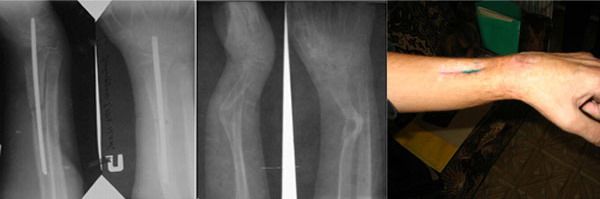

Больной Р. 16 лет, в декабре 2005 г. получил травму в результате падения с турника.Диагноз: з/ перелом обеих костей левого предплечья со смещением. Произведено иссечение свища, дренирование, антибиотикотерапия. Воспалительный процесс купировать не удалось, развился остеомиелит.На сегодняшний день следующая картина. Гипотрофия мышц левого предплечья, в области перелома втянутый рубец, дефект мягких тканей. Ограничение движений ротация - 4-5°, сгибание в лучезапястном суставе - 10/170/10.На рентгенограмме отмечается угловая деформация н/3 левой лучевой кости с углом открытым кнаружи, ложный сустав в области перелома, сужение диаметра меньше 1/3.Был бы очень признателен, получив Ваши суждения по данному поводу. С уважением,Равиль Абдулаев!

Такое ощущение, что часть истории выпала - между падением с турника и иссечением свища явно были какие-то события, да и рентгенограмма с

интрамедуллярным стержнем есть. Можно ли сделать сегодняшние рентгенограммы с большим разрешением?

Остеомиелит развился после остеосинтеза, стержень удален.Далее проходил лечение в гнойно-септическом отделении.Проведена секвестрэктомия,соотвест. терапия. После купирования воспаления "реабилитация" в домашних условиях.На сегодняшний день контрактура в л/з суставе, выраженная гипотрофия,втянутый рубец в области перелома.Предложение об аппаратном лечении представляется логичным и наверное единственно приемлимым.Привет обязательно всем передам.